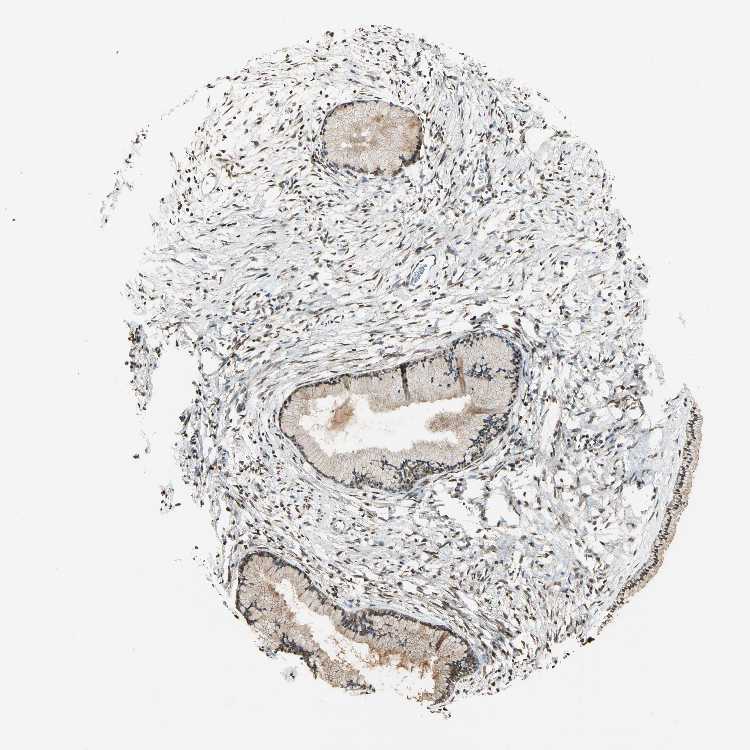

TISSUE PRIMARY DATA CERVIX Show tissue menu

Cervix

CERVIX - Expression summary

CERVIX - Antibody stainingi

Antibody staining in the annotated cell types in the current human tissue is reported as not detected, low, medium, or high, based on conventional immunohistochemistry profiling in selected tissues. This score is based on the combination of the staining intensity and fraction of stained cells.

Each image is clickable and will lead to virtual microscopy that enables deeper exploration of all samples and also displays staining intensity scores, fraction scores and subcellular localization as well as patient and tissue information for each sample.

Antibody HPA003162Antibody CAB005191

Glandular cells MediumMedium

Squamous epithelial cells -Medium